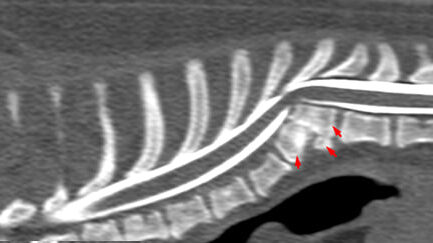

Кифотическая деформация позвоночника у 7,5-месячного мопса: почему мы выбрали TVDS — и что показала практика

Меня зовут Спартак Кравченко, я ветеринарный нейрохирург. Работаю в клинике «Биота» (Омск). Сегодня расскажу не просто «историю выздоровления», а клинический случай с анализом выбора тактики, основанной на современных данных и собственном опыте. Речь пойдёт об Оддине — мопсе, 7,5 месяцев, поступившем к нам в ноябре 2025 года с признаками проприоцептивной атаксии тазовых конечностей. Владелица заметила, что у щенка «заплетается» лапы. Самочувствие — хорошее, мочеиспускание — произвольное. На КТ с миелографией мы увидели: Для справки: согласно исследованию Picón et al...